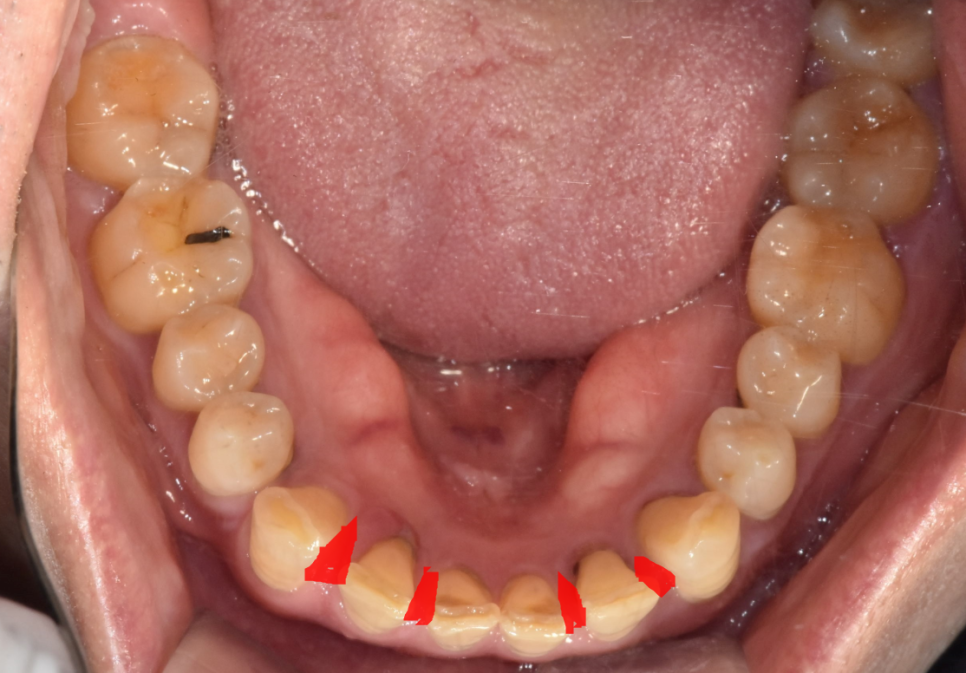

오늘 환자분은 위아래 앞니 모두 사이 사이 공간이 있었습니다.

벌어진 공간이 꽤 컸기 때문에

레진이나 라미네이트로는 한계가 있었습니다.

치아 사이즈가 더 커져서

비슷한 크기로 조화롭게 치료하기 위해서는

앞니를 크라운 치료를 통해 벌어진 것을 메꾸기로 했습니다.

위아래 4개씩 치아를 삭제하여 공간을 재분배